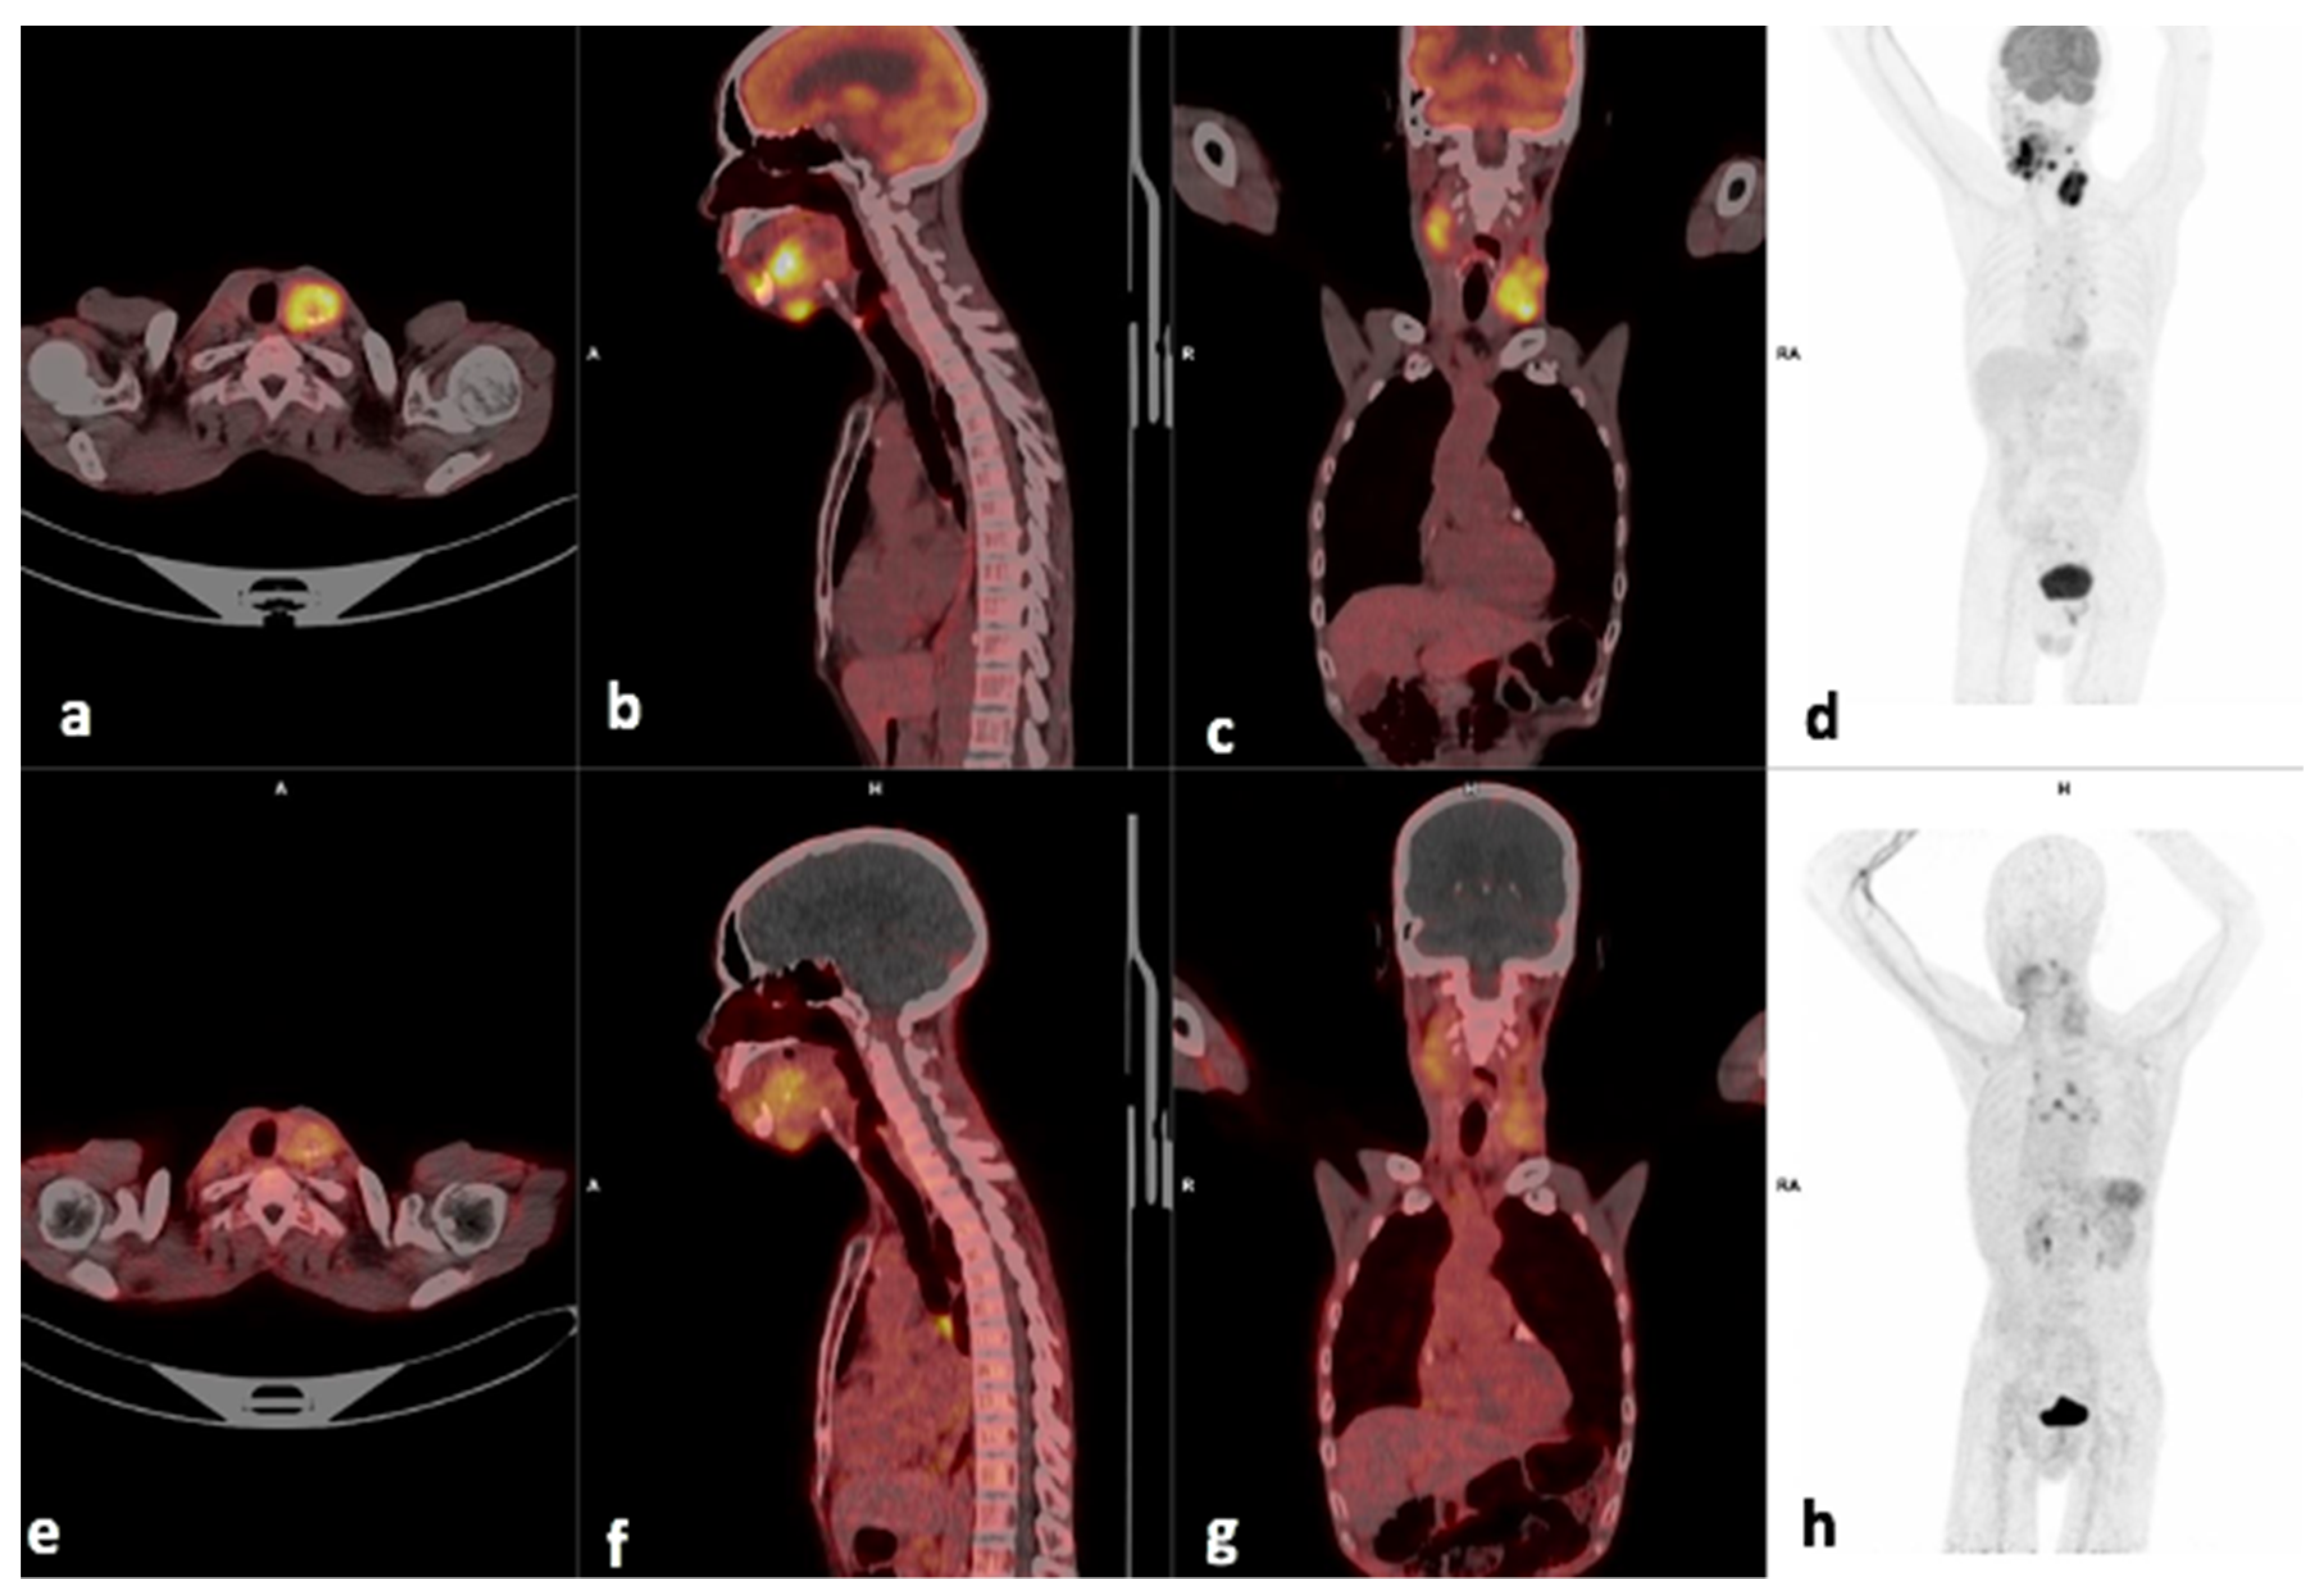

3.2. Comparison of FDG and 68Ga-Pentixafor

3.3. Visual Analysis